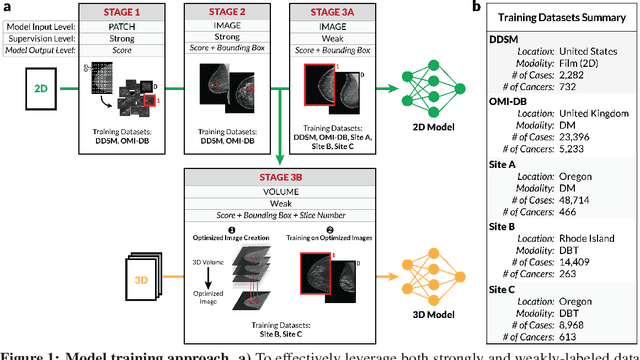

Robust breast cancer detection in mammography and digital breast tomosynthesis using annotation-efficient deep learning approach

Dec 27, 2019

Breast cancer remains a global challenge, causing over 1 million deaths globally in 2018. To achieve earlier breast cancer detection, screening x-ray mammography is recommended by health organizations worldwide and has been estimated to decrease breast cancer mortality by 20-40%. Nevertheless, significant false positive and false negative rates, as well as high interpretation costs, leave opportunities for improving quality and access. To address these limitations, there has been much recent interest in applying deep learning to mammography; however, obtaining large amounts of annotated data poses a challenge for training deep learning models for this purpose, as does ensuring generalization beyond the populations represented in the training dataset. Here, we present an annotation-efficient deep learning approach that 1) achieves state-of-the-art performance in mammogram classification, 2) successfully extends to digital breast tomosynthesis (DBT; "3D mammography"), 3) detects cancers in clinically-negative prior mammograms of cancer patients, 4) generalizes well to a population with low screening rates, and 5) outperforms five-out-of-five full-time breast imaging specialists by improving absolute sensitivity by an average of 14%. Our results demonstrate promise towards software that can improve the accuracy of and access to screening mammography worldwide.